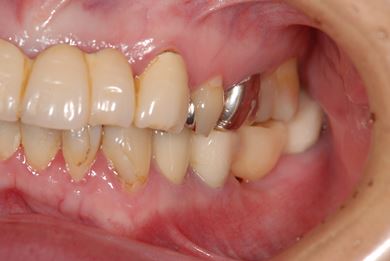

インプラントの症例写真 IMPLANT

骨再生インプラント治療

| 治療方針 | 右下奥、骨再生法によりインプラント治療を可能にする。 | ||||||||||||||||||||||||||||||||

| 治療内容 | インプラント3本(GBR、テンポラリーインプラント+仮歯)、ハイブリッドセラミックブリッジ3本、ハイブリッドセラミッククラウン2本 | ||||||||||||||||||||||||||||||||

| 総治療費 | 1,524,338円 | ||||||||||||||||||||||||||||||||

| 治療期間 | 1年0ヶ月 |